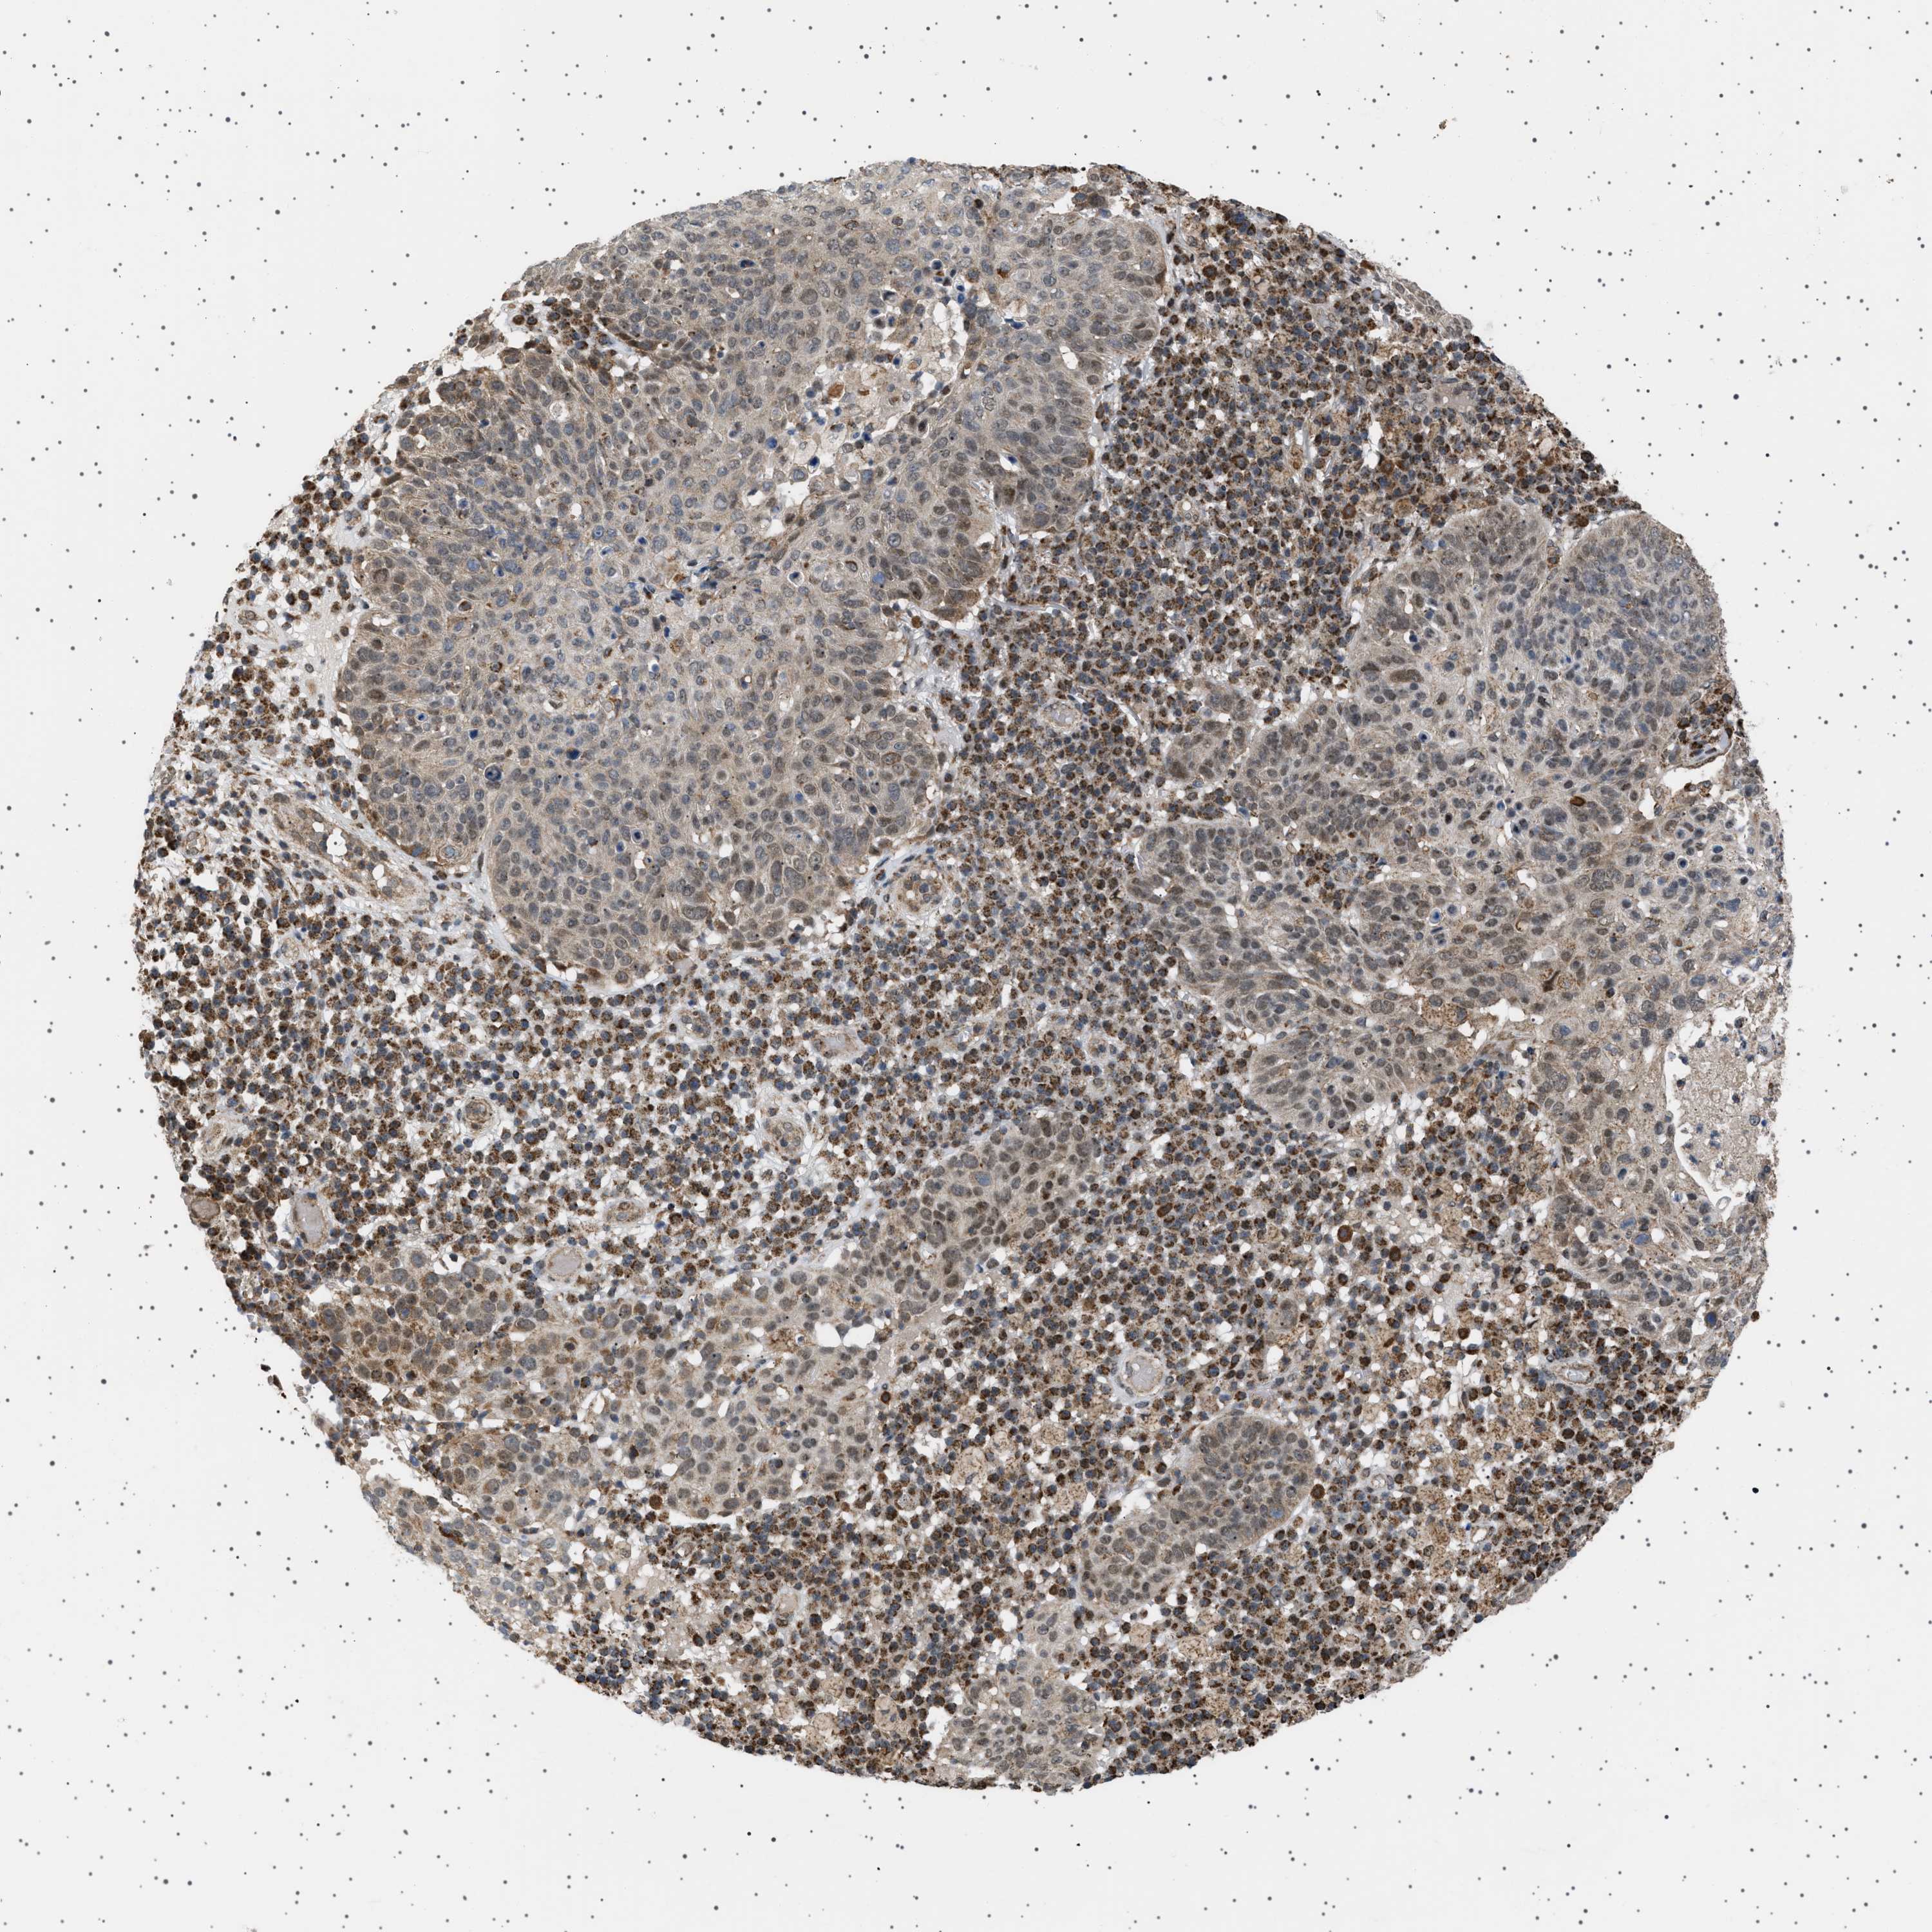

SKIN CANCER - Protein expressioni

A mouse-over function shows sample information and annotation data. Click on an image to view it in a full screen mode. Samples can be filtered based on level of antibody staining by selecting one or several of the following categories: high, medium, low and not detected. The assay and annotation is described here.

Each image is clickable and will lead to virtual microscopy that enables deeper exploration of all samples and also displays staining intensity scores, fraction scores and subcellular localization as well as patient and tissue information for each sample.

Antibody HPA017214

Staining

Low

Intensity

Weak

Quantity

<25%

Location

Nuclear

Basal cell carcinoma